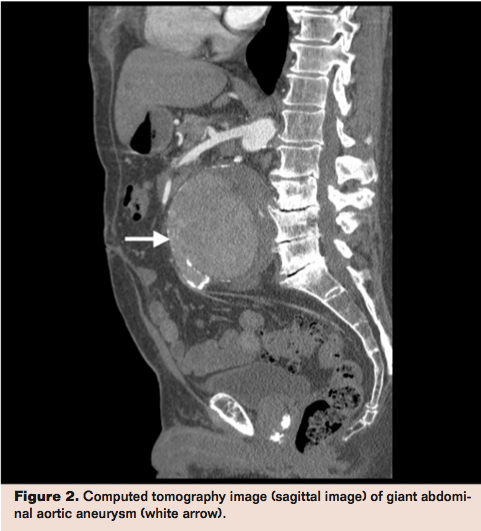

Computed tomographic angiography of the abdomen after administration of intravenous contrast showed a giant juxtarenal abdominal aortic aneurysm (AAA) measuring 14 cm in diameter (Figures 1 and 2, arrows) without any evidence of rupture. He was sent to the hospital for urgent vascular surgical treatment. On admission, his exam was unchanged and the laboratory data showed mild chronic anemia and normal creatinine.